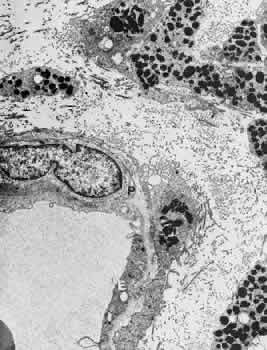

| Although investigation of the blood-brain barrier was initiated in the

first decade of the 20th century, the blood-retinal barrier was not defined

until much later.165 Information accumulated during the past two decades has shown that the

function of the blood-ocular barrier may be better understood if two

main barrier systems are considered to exist in the eye. The blood-aqueous

barrier regulates the exchanges between the blood and the intraocular

fluids, and the blood-retinal barrier separates the neural tissue

from the blood. These barriers are essential for the control of the microenvironment

of the ocular tissues. They prevent noxious water-soluble

molecules from entering the extravascular spaces of the eye and impede